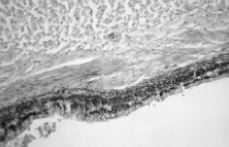

El informe anatomopatológico de la pieza fue de teratoma maduro intrauterino con áreas de diferenciación linfoide, intestinal y pulmonar. (Figs. 1, 2 y 3).

Figura 3. Epitelio respiratorio contenido en el teratoma.